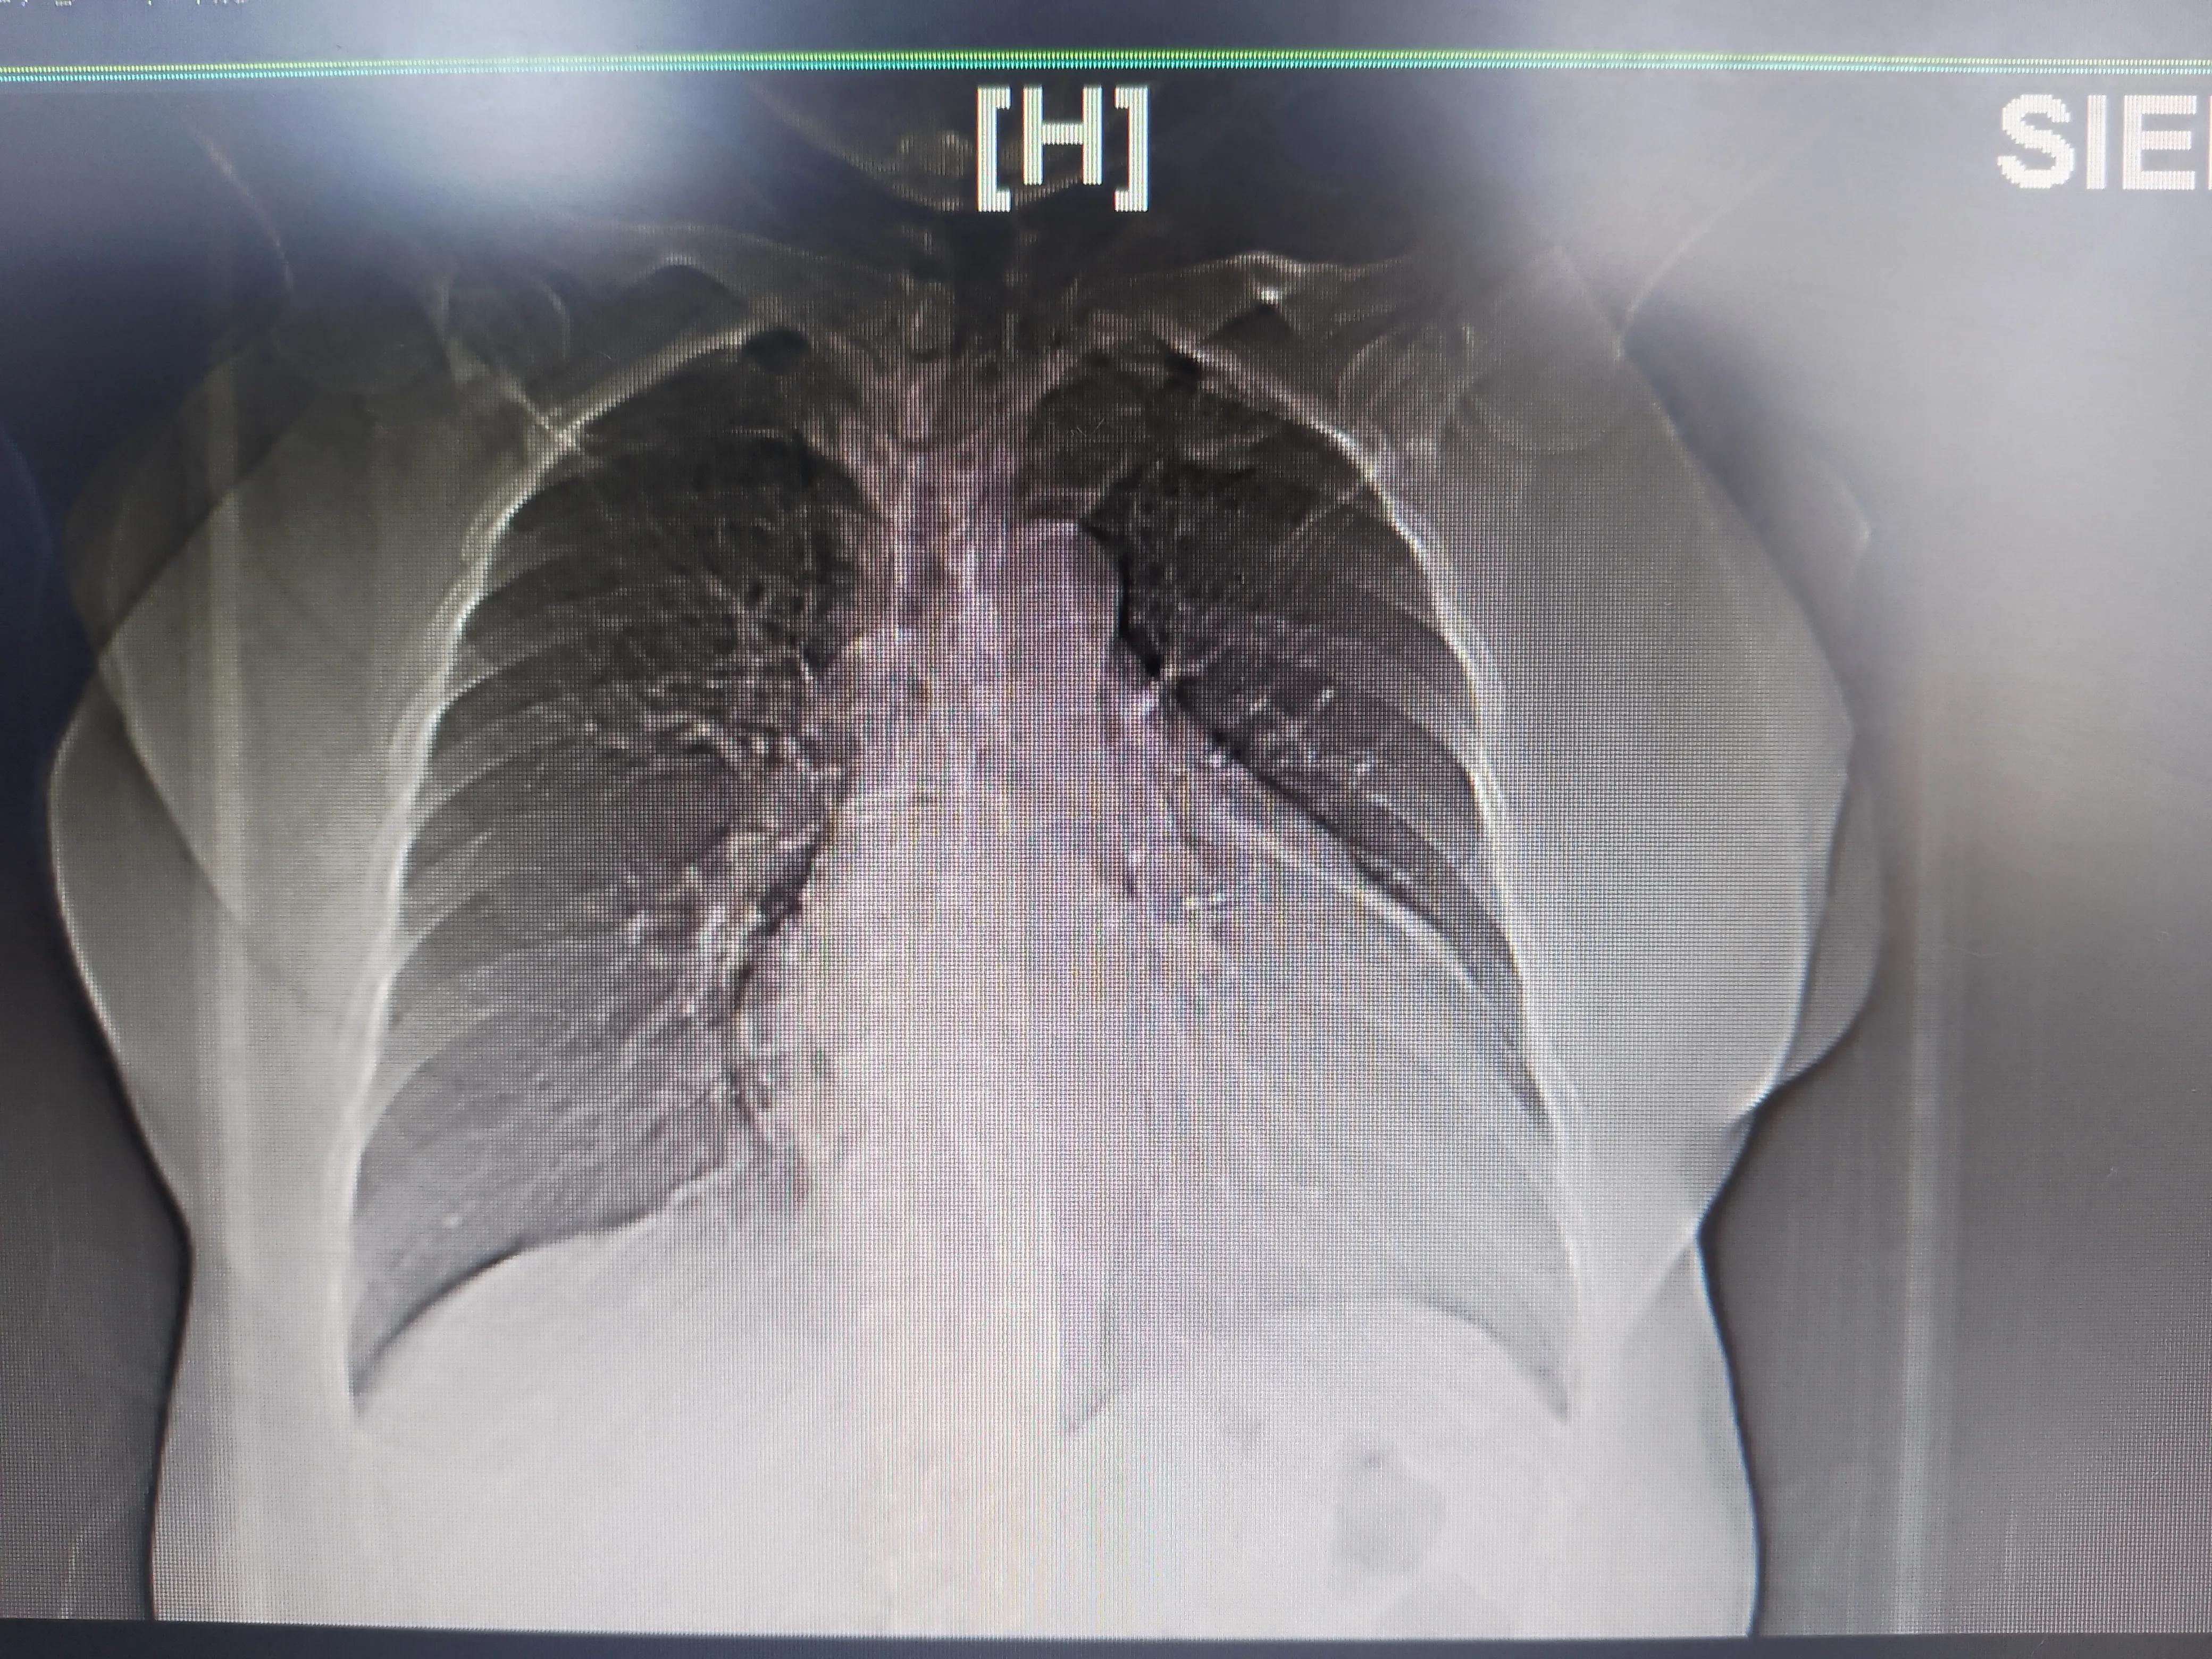

她两年多来一直反复胸闷气喘,2021.11到上海十院就诊,我们初诊发现是个房颤,并且2018.2仍然有窦性心律心电图,提示是个短程持续性房颤(持续超过1周但不超过1年的房颤)。患者又有腔梗病史,因此我们当时考虑可能是心律失常引起的。虽然当时心超已经提示“右心房很大”。而且不到一年的持续房颤已经心率不快了。

后来她电话联系我,我第一反应还以为是房颤消融的罕见并发症(肺静脉闭塞或膈肌麻痹),后来调了资料才发现做消融那会已经有“右心扩大,肺动脉高压(中度)”。心电图除了房颤外,还有R波递增不良,请病人再次入院,排除下心脏缺血:

同时肺静脉CT里面发现肺里很干净,没有结节也没有明显的急性或慢性炎症;右心明显扩大导致心尖上翘。

右心明显扩大

右心明显扩大,肺挺干净的